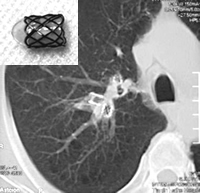

本报讯 天津市呼吸疾病研究所吴琦等应用国产支架,为1例(62岁男性)慢性阻塞性肺病(COPD)患者进行纤维支气管镜肺减容术(BLVR)治疗,获得满意疗效。

BLVR是使用纤维支气管镜在支气管内放置活瓣支架以形成医源性肺不张从而达到内科肺减容的目的。吴琦等共为患者放置了6枚支架。术后2周时,患者已可平卧睡眠,临床症状、肺功能、6分钟步行试验均明显改善,无心、肝、肾功能改变及严重并发症。影像学检查支架位置良好,支架远端支气管聚拢。